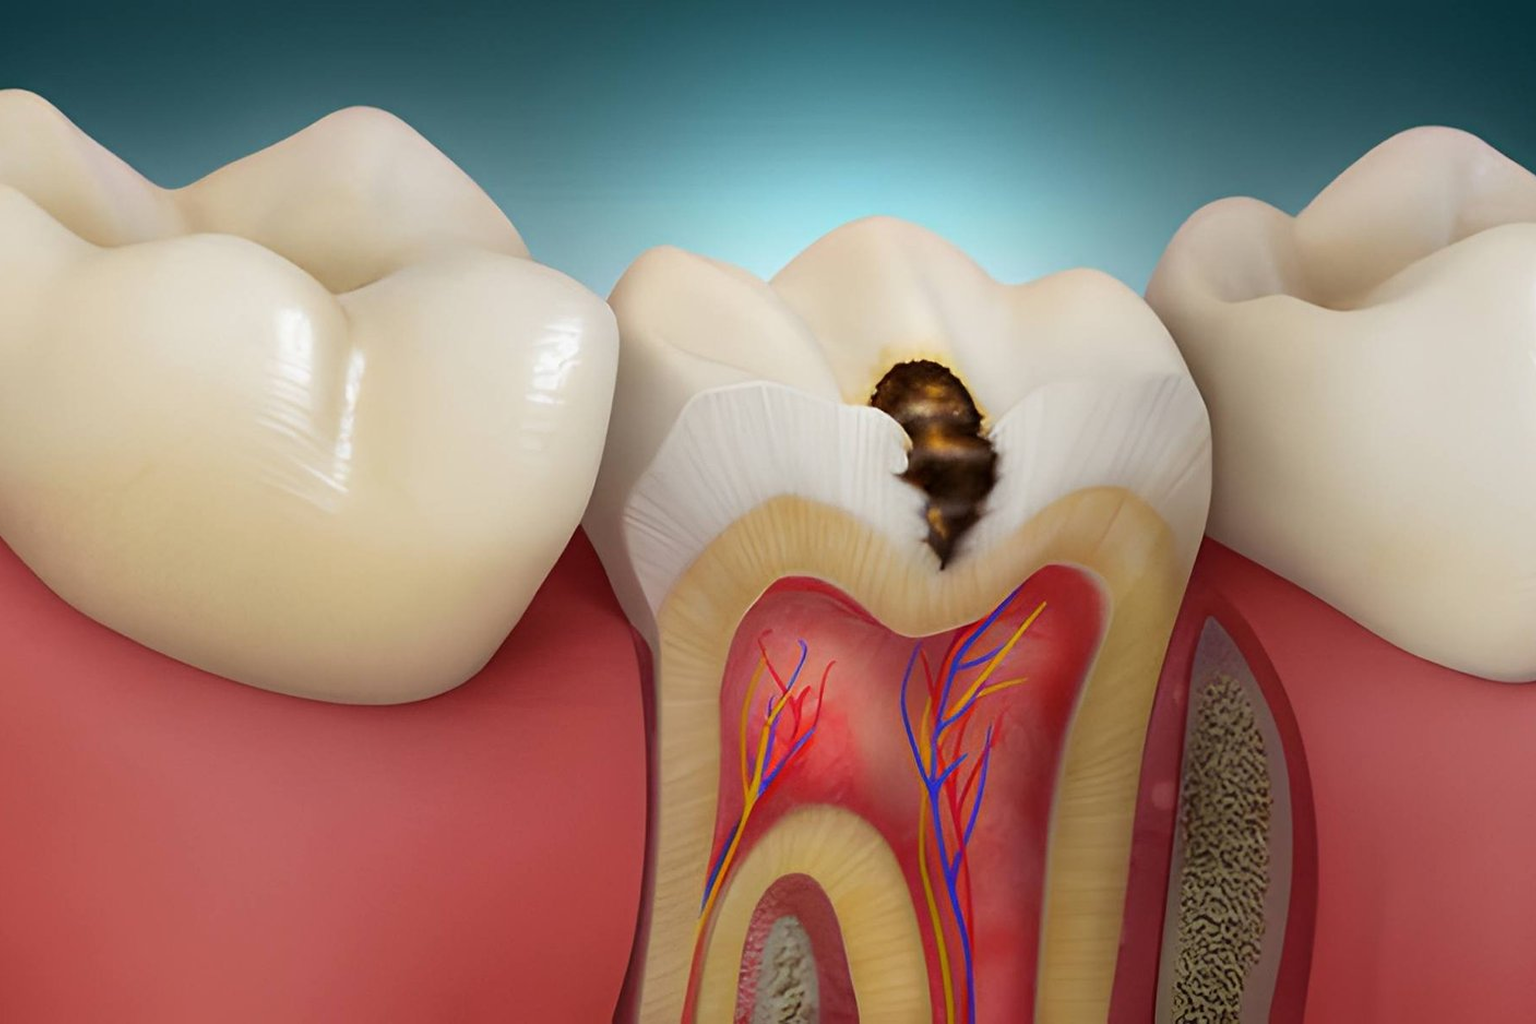

- PROBLEMS & SYMPTOMS :

Dental problems that may require composite fillings

- Tooth decay or cavity formation

- Minor cracks or chipped tooth edges

- Sensitivity from weakened enamel

- Visible tooth discoloration or wear

- Small structural damage to teeth